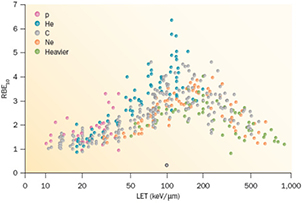

Cell survival studies showed already many years ago (Blakely et al 1984) that heavy charged particles have an increased relative biological effectiveness (RBE) compared to x-rays, mostly described by an increase in the α parameter, resulting in steeper survival curves. The RBE is defined as the ratio Dx/Dp of the x-ray and particle radiation doses giving the same biological effective—e.g. 10% cell survival (RBE10). The RBE depends on several physical (LET6, dose, dose rate, fractionation, particle mass etc) and biological (intrinsic radiosensitivity, biological endpoint, oxygen concentration, cell cycle phase, proliferation rate, etc) parameters (Durante and Loeffler 2010). Data mining of RBE values (Friedrich et al 2013) from cellular experiments performed in the past 50 years with different ions always shows a large variance (figure 8). The general trend is always the same: an increase from low-LET up to 100–200 keV μm−1, and then a decrease at very high-LET caused by the overkilling effect. Light particles are generally more effective than heavy particles at the same LET, because they are slower and therefore have a narrow track width. The biological advantages of irradiating a tumor with a high-LET ion goes beyond the RBE for cell killing: the oxygen enhancement ratio (OER), cell-cycle variation in sensitivity, and sparing by fractionation are reduced with densely ionizing radiation, making CPT ideal against hypoxic tumors, or with many proliferating cells. More evidence is also accumulating showing that high-LET radiation has distinct radiobiological effects compared to low-LET, e.g. reducing angiogenesis and cell migration (Loeffler and Durante 2013). Taken together, these data suggest that using a charged particle with low-LET in the entrance channel (high velocity) but of relatively high-LET in the SOBP (low velocity) will provide a further biological improvement to the treatment beyond the physical advantages.

Figure 8. RBE compared with LET from published experiments on in vitro cell lines. RBE is calculated at 10% survival, LET values are given is keV μm−1 in water. Different colours indicate different ions, from protons to heavy ions. Data points are extracted from the particle radiation data ensemble (PIDE) database (Friedrich et al 2013), which currently includes 855 survival curves for cells exposed to photons (α/β ratio ranging 1–30) and ions. PIDE is available online at www.gsi.de/bio-pide. Figure from Loeffler and Durante (2013), copyright 2013 reproduced with permission from the Nature Publishing Group.

Download figure:

Standard image High-resolution imageProtons used in therapy generally have an entrance energy between 150 and 250 MeV (15–35 cm range in water), corresponding to a low-LET in water around 1 keV μm−1. The LET on the SOBP increases with depth in a range of 2–6 keV μm−1 (Paganetti 2014). It is expected that this modest LET increase will correspond to an increased RBE (figure 9), using the data from the same PIDE database shown in figure 8 (Tommasino and Durante 2015). However, the effect is arguably significant only in the last few mm of the SOBP. Thus, the proton therapy community has adopted a constant RBE of 1.1, which seems to be reasonable considering the unavoidable spread associated to RBE estimates (Paganetti 2002). A significant increase in RBE, and other special high-LET radiation effects, in the SOBP-tumor volume can only be achieved using heavier ions, where the LET reaches the maximum value in figure 8. For this very reason, Cornelius A. Tobias proposed using different heavy ions during the clinical trial at the Lawrence Berkeley Laboratory 1975–1992: He, Ne, N, O, C, Si, and Ar (Castro 1995). The use of very heavy ions, such as argon, was justified by the goal of overcoming hypoxia, which requires very high-LET according to the cell experiments performed at the Bevalac accelerator in Blakely et al (1984). However, the entrance LET for this very heavy ions is already quite high, and an increased NTCP was observed. Carbon represents a good compromise, with an LET in the entrance channel between 11 and 13 keV μm−1, and a fairly high LET on the SOBP between 40 and 90 keV μm−1.